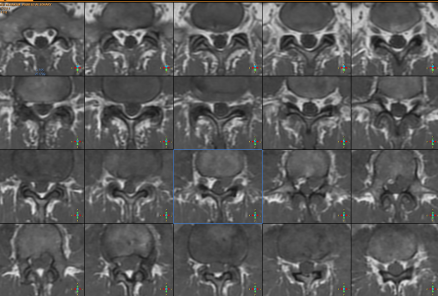

28-MAY-2014  ABDEL-HAKIM WAHEED AL-JOHARY  57 YEARS  EXTRUDED DISC L2-3 WITH LEFT DOWNWARD MIGRATION.

The patient came to the clinic 27-May-2014 complaining of left sciatica with LBP for 3 weeks with pain to above and below the left knee with sudden onset. CT-scan of the lumbar spine done  10-May-2014 showing spondylolisthesis L4-5. MRI lumbar spine done 17-May-2014 showing very huge extruded disc L2-3 with left far downward migration.

On examination; The patient is not limping. SLRS was 85 degrees in the left with pain. There is weak dorsiflexion left foot 4/5 and the left quadriceps +4/5. The left knee jerk is diminished.

MRI showing the huge extrusion of L2-3 with left far downward migration reaching the L3-4 level.